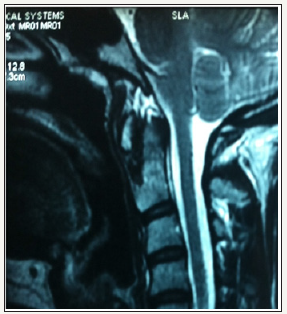

Simple radiography (Rx) revealed the existence of a partial defect in the posterior arch of C1 with a preserved posterior tubercle (Currarino type D) (Figure 1). We verified the stability of the tubercle through radiography in flexion and extension (Figure 2). Computed tomography (CT) images with three-dimensional (3D) reconstruction demonstrated the absence of the posterior arch and the presence of a persistent posterior tubercle (Figure 3). No evidence of compression of the spinal cord was shown on magnetic resonance imaging (Figure 4). The patient benefited from a symptomatic treatment with anti-inflammatory and analgesic drugs. Her symptoms decreased within 48 hours. She was asked to avoid contact sports, athletic activities and any activity or situation which could cause the cervical hyperextension.

Figure 4: Sagittal T2-weighted magnetic resonance imaging revealing no compression of the spinal cord.

Alterations of the posterior arch of the atlas are rare (< 4%). This is especially true of type D cases, such as the case presented in this work, which have a prevalence under 0.2% [1]. When not associated with a syndrome (Down, Turner, Di Giorge, etc.), these patients are usually asymptomatic and the finding is incidental [5], mostly due to imaging studies performed after trauma or chronic neck pain. Computed tomography is useful to confirm the diagnosis and differentiate it from fractures in particular the fracture typifies Jefferson. Magnetic resonance imaging is reserved for cases where any neurologic abnormality is observed or there is a suspicion of myelopathy.